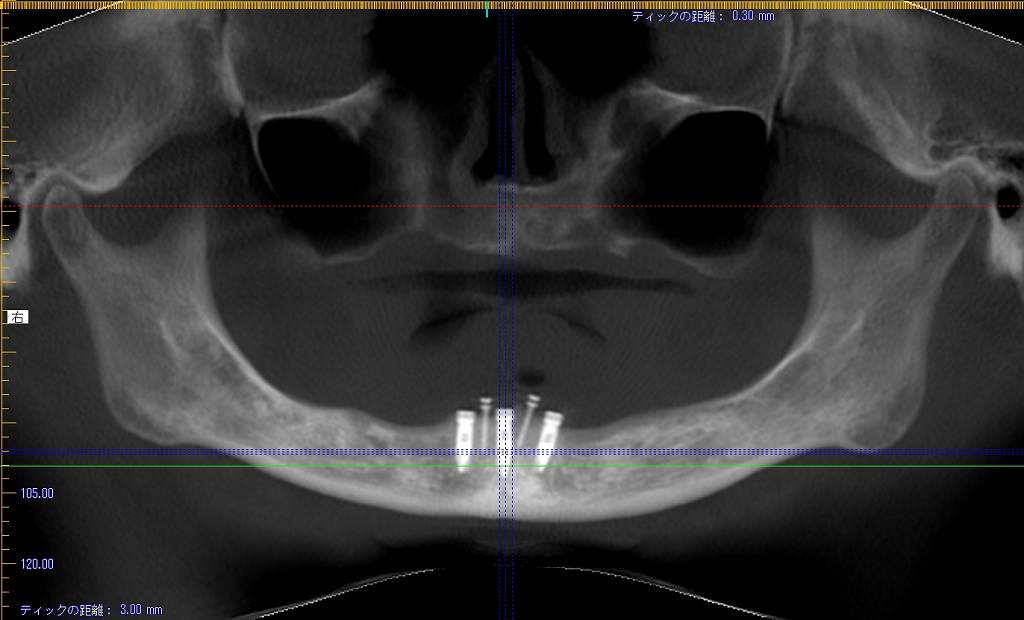

インプラント埋入時になります

3本とも4mmの13mmというインプラントを埋入

術前術後のパノラマになります

インプラントはオペ時に5本入れていることになります